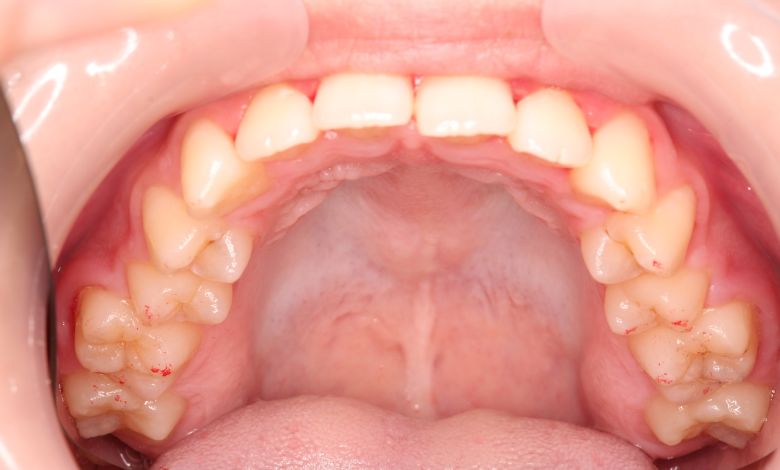

上顎歯列はV字型に近く、全体的にアーチが狭窄している状態

叢生が解消され、歯列全体にわたり滑らかで調和のとれた配列が得られています

歯列弓はV字型に狭く、左右の犬歯が唇側に大きく転位している状態

歯列弓はV字型から自然でゆったりとしたU字型へと広がり、唇側に転位していた犬歯も正しい歯列内に整列されています。

歯並びがV字型で歯茎の土手(歯列弓)が狭く、歯が並ぶスペースが狭い

歯並びがU字型になって、歯茎の土手(歯列弓)が広くなった。

前歯の重なりが大きい

前歯の重なりがなくなって、綺麗な歯並びになった。